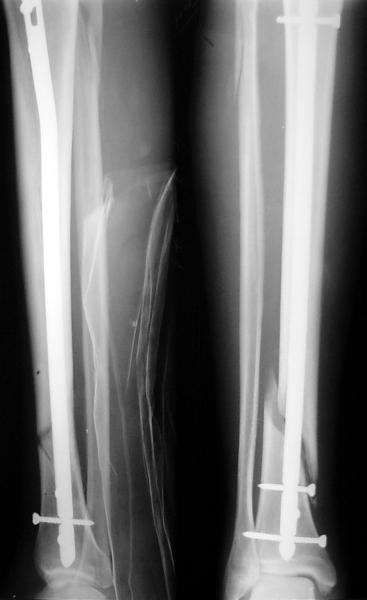

На мой взгляд, на снимках, приведённых Вами - неправильно сростающийся перелом дистальной трети большеберцовой кости, состояние после остеосинтеза интрамедуллярным гвоздём.

Как Вы пишите снимок под номером 1 - менсяц после операции, под номером 2- два месяца после операции.

Вы не послали послеоперационный снимок, поэтому трудно судить о состоянии редукции после операции.

I think that the X-Rays show S/P IMN of Spiral # of the Distal Tibia consoles in misalignment.

You wrote that a picture number 1 - f month after the surgery, and number 2-two months after the surgery.

You have not sent a postoperative X-Rays; so it's impossible to discuss about the condition of a reduction after operation.

Let to express concerning technique of operation my opinion... Insertion of a screw to medial side of a nail in distal fragment would help you to reduction and to keep this fracture in anatomic position has prevented varus deformity and displacement on width. By the way, if it is possible send a postoperative picture.